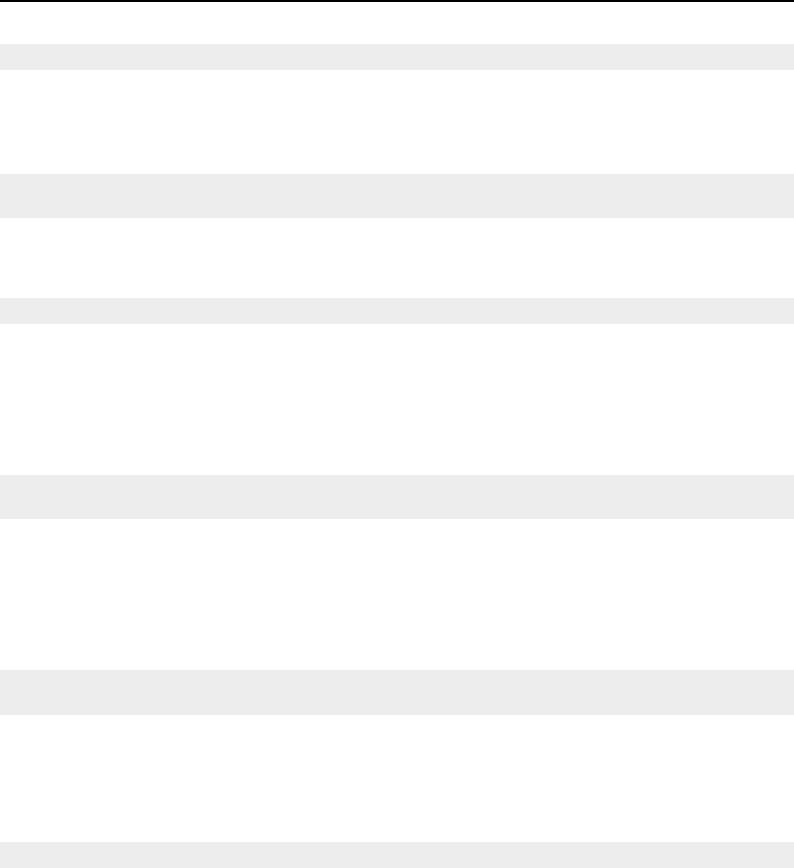

- Thresholding

- Segmentation